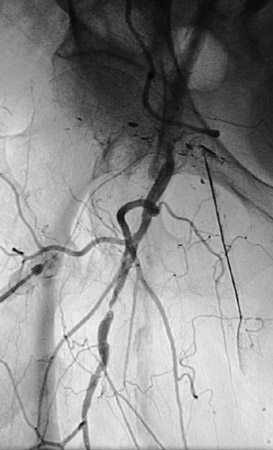

The angiogram views above and below reveal multiple areas of atherosclerotic narrowing involving branches of the right femoral artery.